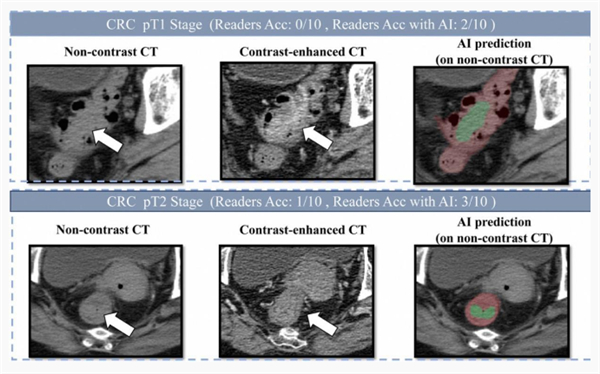

【阿里发布第三个癌症AI模型:接连突破胰腺癌、胃癌、肠癌筛查难题】据媒体报道,阿里巴巴达摩院联合广东省人民医院等机构,成功研发出肠癌筛查AI模型——DAMO COCA。该模型能够在2.7万人的平扫CT影像中精准识别出5例漏诊的肠癌,敏感性和特异性分别达到86.6%和99.8%。这在国际上首次提出了一种无需肠道准备、患者“无感”的肠癌机会性筛查方法。

为此,达摩院发挥其多年在“平扫CT+AI”领域的技术积累,采用“先定位、后诊断”的两阶段深度学习架构和混合监督学习策略,并针对小于3厘米的早期肿瘤进行专门训练。这使得AI模型能够精细分割形态复杂的肠道区域,有效克服内容物干扰,精准检测可疑病灶。

研究团队发表在欧洲肿瘤内科学会官方期刊《肿瘤学年鉴》(Annals of Oncology,影响因子65.4)上的论文显示,DAMO COCA模型的敏感性(防止漏诊的能力)达86.6%,特异性达99.8%,即误诊率仅为0.2%。